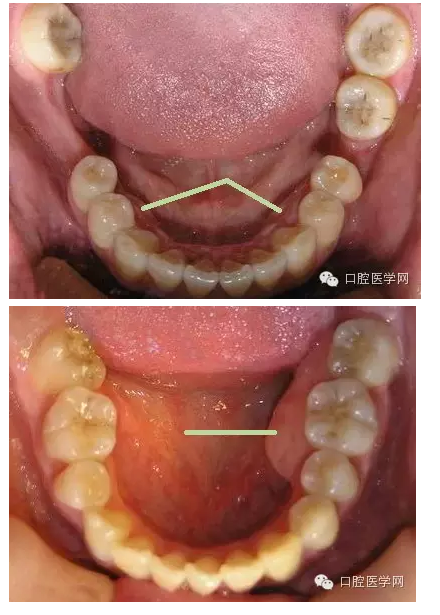

在臨床上我們需要把牙槽骨增生和骨隆突區(qū)分開來,骨隆突是在頜骨上的生理性骨性突起,并不是一個疾病癥狀,也不是疾病的表現(xiàn),比如舌側(cè)骨隆突、上頜骨骨隆突、下頜隆突是在第三磨牙和雙尖牙舌側(cè)的一個生理性突起。